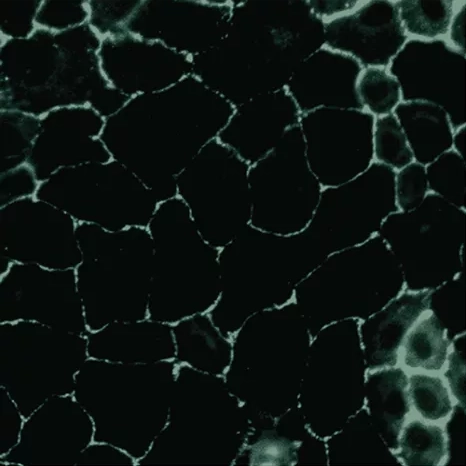

While ION* works in several ways to counteract the effects of gluten at the gut lining, gluten is where this innovative humic extract blend really shines. The molecules that make up ION* help to activate the enzyme, DPP4, which works to remove the toxic peptides found in gluten. By sparking this initial enzyme production, ION* can maintain low levels of zonulin and combat tight junction damage. And by maintaining tight junction integrity, even in the face of glyphosate toxicity, ION* is further helping to defend against unnecessary immune response associated with gluten exposure.

By reducing free radical damage and upregulating enzymes that help degrade gliadin peptides, ION* Gut Support helps to protect the gut lining against damage from gluten, further defending your immune system from the onslaught of inflammatory foods and toxins.